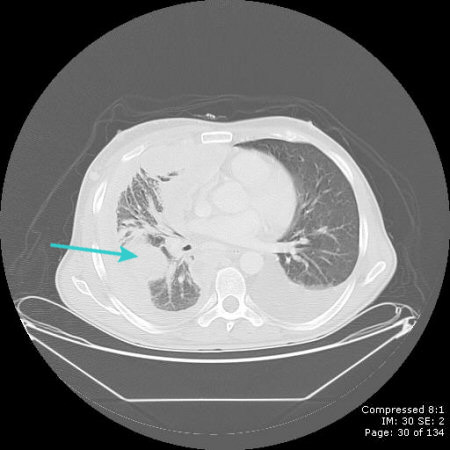

CT scan showing metastatic malignancy of pleura

From the collection of Dr Ami Rubinowitz; used with permission